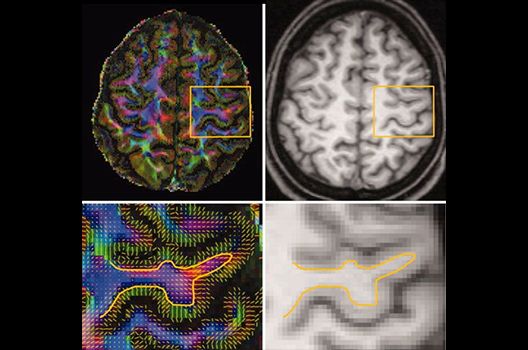

- MR-Diffusionstensorbildgebung (Faserbahndarstellung/fiber tracking)

Die Schwerpunkte in der MR-Forschung liegen in der multiparametrischen und funktionellen Bildgebung bei onkologischen und anderen, neuroradiologischen Fragestellungen und umfassen die Anwendung modernster MR-Verfahren sowie die Untersuchung an Hochfeld-Geräten.

Die Magnetresonanztomographie (MRT) ist ein Verfahren, bei dem durch magnetische Kräfte Bilder des Körperinneren angefertigt werden. In der Neuroradiologie können manchmal kleinste Veränderungen schwere Folgen haben; daher forschen wir an der Entwicklung hochauflösender MRT-Sequenzen, mit denen diese Prozesse und auch einzelne Nervenfaserbahnen sichtbar gemacht werden können. Darüber hinaus sind bei vielen Erkrankungen des Gehirns die Blutgefäße betroffen. Daher arbeiten wir an der Neu- und Weiterentwicklung von MRT-Sequenzen zur Darstellung der Blutgefäße und zur Blutflussanalyse (sog. „Angio-MRT“). Einen besonderen Forschungsschwerpunkt unserer Klinik stellen die MR-Protonenspektroskopie und die funktionelle MRT dar, mit denen die Analyse einzelner chemischer Substanzen im Hirngewebe oder die Darstellung ausgewählter Hirnfunktionen möglich ist.